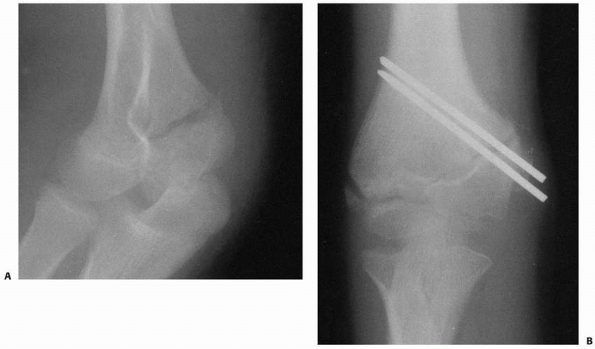

![]() |

FIGURE 15-9 Stage II fracture of the lateral condyle. A.

AP radiograph shows 4 mm of displacement of the metaphyseal segment; however, the fracture was stable by stress examination and arthrography. B. Four weeks after percutaneous pinning, the fracture is healed. |